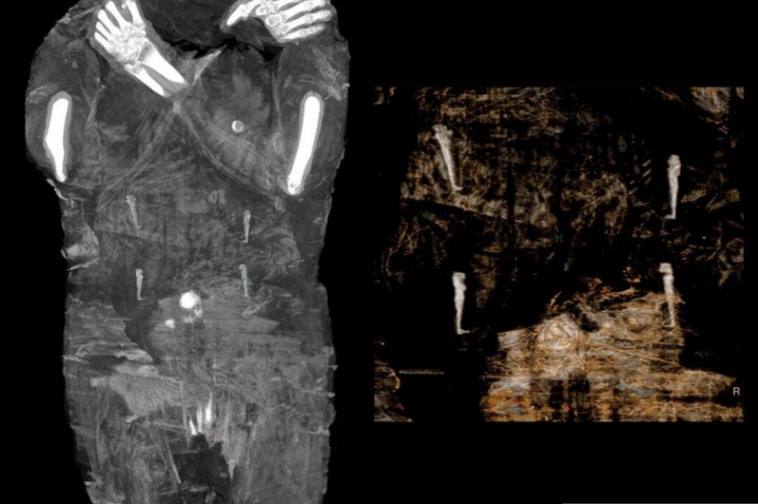

באמצעות היקף ראשו של העובר החוקרים הניחו כי האישה הייתה בין שבוע 26 לשבוע 30 בהריונה, כאשר סיבת המוות לא ידועה. "זהו הממצא החשוב והמשמעותי ביותר שלנו עד היום. הפתעה מוחלטת", אמר חבר הצוות וויצ'י אייזמונד לסוכנות הידיעות רויטרס. כמו כן, החוקרים בחרו לכנות את המומיה המיוחדת כ"גברת המסתורית של מוזיאון וורשה", בעקבות מידע רב שחסר אודותיה.

צילום הרנטגן של המומיה

צילום הרנטגן של המומיה | צילום: רויטרס